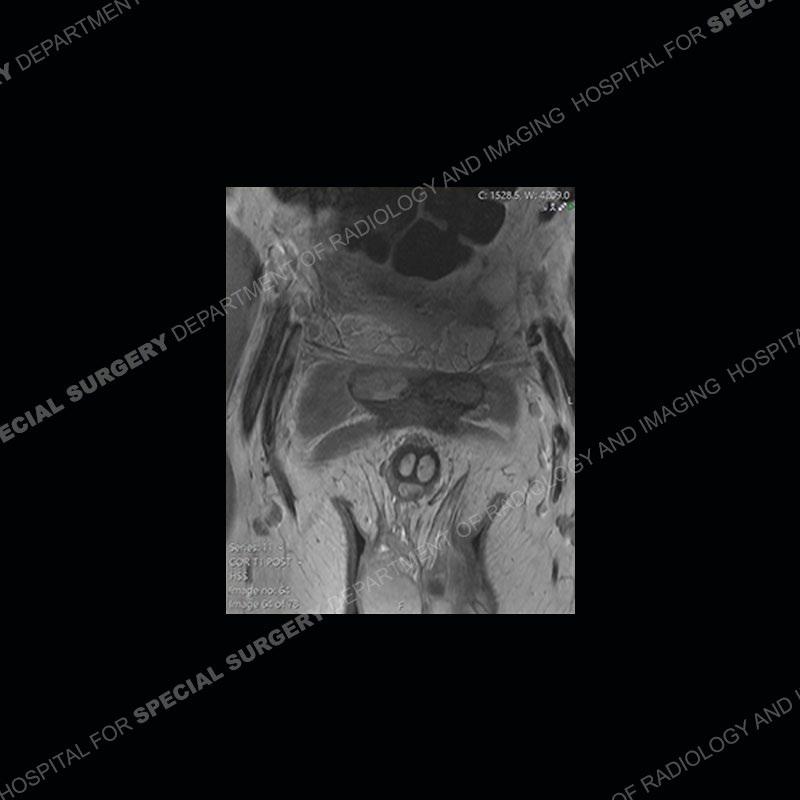

Subsequent MRI in a very short time interval shows markedly increased abnormality of the ramus and increased edema and “mass” of the soft tissue. Post contrast imaging shows multiple, rim enhancing collections of the soft tissue and similar albeit less conspicuous enhancing collection of the ramus.

The repeat MRI, with the marked degree of increased abnormality of the bone and soft tissue shifted the diagnosis to a high degree towards infection. Even the most aggressive of neoplasms would not have that the degree of change in a 3-day time span. The CT study was shown before the repeat MRI but actually occurred just after the repeat MRI. It helped confirm the destructive process of the ramus and particularly the abnormal architecture along the inferior margin. The patient went on to have a CT guided aspiration of one of the soft tissue collections with 4cc of purulent fluid obtained. A surgical irrigation and debridement of the bone and soft tissue was performed. A PICC line was placed and the patient is currently undergoing IV antibiotic treatment with a possible repeat irrigation and debridement.